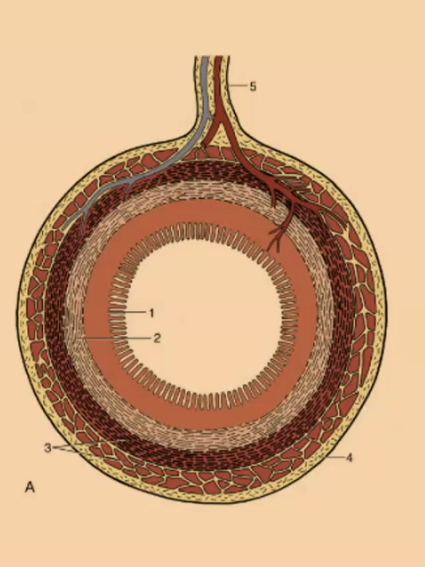

What is the outermost layer of the simple stomach?

Serosa

Serosa

What creates the mucosal folds in the simple stomach?

submucosa

What is the thinnest layer of the simple stomach wall?

Muscularis mucosa

What is the innermost layer of the simple stomach wall?

Mucosa

#1

Mucosa

#2

Submucosa

#3

Muscular (2 Layers)

#4

Serosa